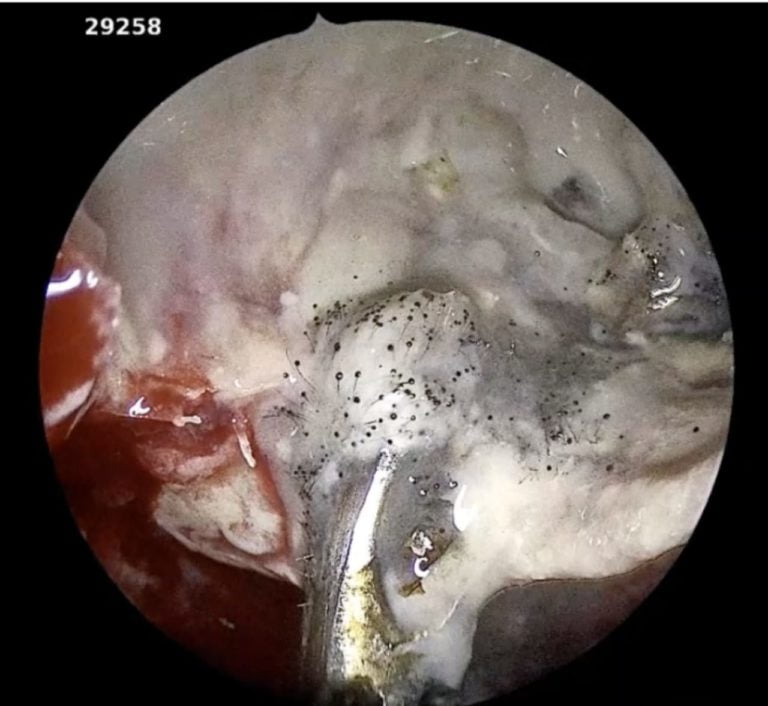

Bhubaneswar: Additional Chief Secretary (Health) PK Mohapatra on Wednesday informed that Odisha has so far reported 140 black fungus or mucormycosis cases. Among them, 20 have succumbed to the fungal ...